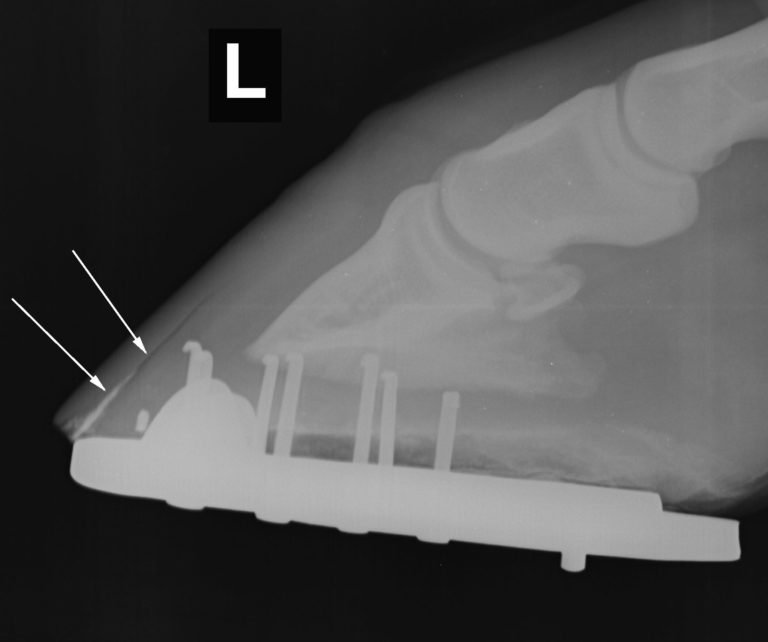

Severe hoof infection penetrated by the white line, infection by anaerobic bacteria (bacteria that can live without oxygen) and fungi that are resistant to local antibiotics and antifungals.

The treatment of this pathology involves eliminating all the affected tissue and invaded by fungi and bacteria, to expose them to the action of a caustic that they completely eliminate.